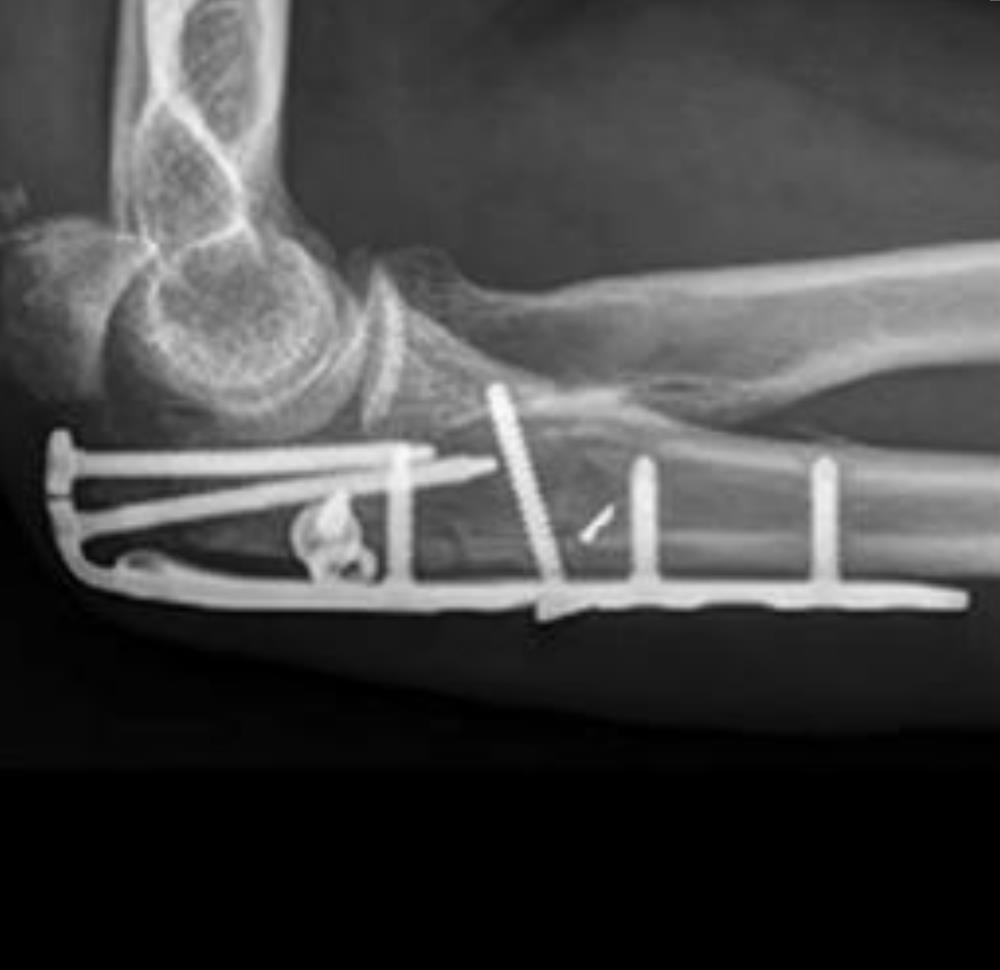

• Fluoroscopic Confirmation

• repeat steps past two steps for the remaining olecranon screw hole using a 3.5mm Multi-Thread Locking Screw

• confirm proper plate positioning, fracture reduction and screw lengths using fluoroscopic imaging

• using fluoroscopic imaging, confirm that proper reduction has been maintained and that all screws are of proper length and fully engaged to the plate

• confirm that all PDGs have been removed.